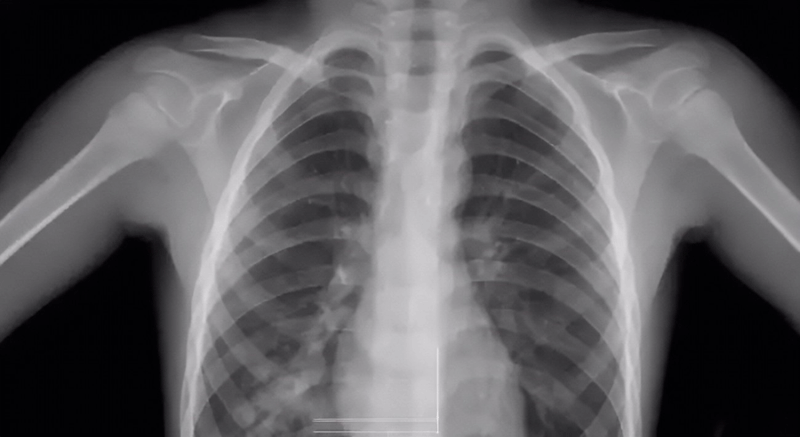

1 胸透检查方式

胸透的检查方式是利用X射线的穿透性、荧光性和摄影效应等特性,使患者的肺部等在荧屏上形成影像。由于人体组织有密度和厚度的差别,所以当X射线穿透人体时,X线被不同程度的吸收了,到达荧屏上的X射线量就有差异,然后形成黑白对比明显的成像,为医生的诊断提供依据。

胸透检查可以查出是否患有肺结核

关于胸透检查方式,很多人都很好奇男女的检查方式是不是一样的,其实,做胸透男女检查的方式都是一样的。不会因为女性特殊一点,就有特殊的检查方法。在检查时,男女身上都会穿着衣服,以及拍出来的成片上显示会有一点点光斑或阴影,但是是不会看到女性的隐私部位的,所以是没有影响的。

关于胸透检查报告

做胸透检查可以查出的项目非常多,它是通过X射线穿透人体的不同层度结合荧光成像来分析人体某部位存在的异常。胸透检查报告的主要内容有:显示肺部是否有疾病、心脏是否有异常、胸膜有无问题、胸壁纵隔、肋骨有无受损、支气管疾病等。

胸透检查报告常见结果分析:

1、两肺未见明显活动性病变:说明肺部非常健康,无病变出现;

2、胸廓无异常,两肺纹理清晰:说明胸部或肺部没有任何异常;

3、两上肺可见斑点状钙化:说明患者以前可能在不知情的情况下得过结核病,但没有发现就自愈了;

4、两肺门影不大:说明肺部和器官都很健康,心脏功能也很正常,若有心脏病,可能会引起肺门水肿;

5、气管、纵隔无偏移:说明颈部和胸腔内没有出现肿瘤或任何异物,如果有肿瘤或异物的话会把气管和纵隔推偏,看起来位置就会发生错位;

6、两肋膈角锐利:说明胸腔内没有积水或渗出液,当出现炎症或结核等病变时会引起积液渗入到胸腔内,使肋膈角变得模糊圆钝;

7、心影形态大小未见明显异常:说明心脏是健康的;

8、膈面光整:腹腔里面的各个小组织没有出现穿孔,因为穿孔会让气体外泄,使膈面下有黑影。